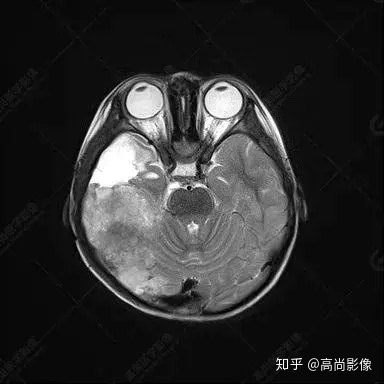

右側(cè)顳葉腫瘤切除術(shù)后(具體不詳):右側(cè)顳部骨質(zhì)不連續(xù)呈術(shù)后改變,右側(cè)顳葉術(shù)區(qū)見片狀長T1長T2信號影,F(xiàn)LAIR呈低信號;術(shù)區(qū)后方右側(cè)顳枕葉見一巨大占位性病變影,邊界欠清,大小約6.2×5.8×4.3cm(前后×左右×上下),信號不均勻,T1WI呈等稍低信號間雜少許高信號,T2WI呈高稍低混雜信號,DWI示部分病灶彌散受限,相應(yīng)ADC圖減低,磁敏感序列見部分呈極低信號,增強(qiáng)掃描可見明顯不均勻強(qiáng)化,鄰近硬腦膜及小腦幕增厚并明顯強(qiáng)化;另延髓右前方及右側(cè)橋小腦角區(qū)見一不規(guī)則形異常信號影,大小約3.2×1.3×3.7cm(左右×前后×上下),呈長T1稍長T2信號,F(xiàn)LAIR呈等信號,DWI未見受限,增強(qiáng)后明顯均勻強(qiáng)化,鄰近腦膜明顯強(qiáng)化。鄰近腦實質(zhì)及右側(cè)顳角明顯受壓;左側(cè)大腦半球未見局灶性信號異常,中線結(jié)構(gòu)稍左移。

右側(cè)顳葉腫瘤切除術(shù)后:現(xiàn)術(shù)區(qū)后方右側(cè)顳枕葉及延髓右前方占位,右側(cè)顳枕部硬腦膜及小腦幕明顯強(qiáng)化,結(jié)合既往影像資料,考慮為胚胎源性惡性腫瘤,如非典型畸胎樣/橫紋肌樣瘤(AT/RT)或原始神經(jīng)外胚層腫瘤(PNET)。

術(shù)后隨訪病理結(jié)果:非典型畸胎樣/橫紋肌樣瘤。